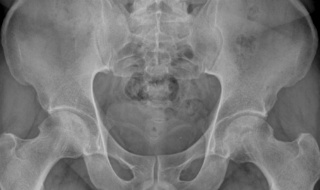

2011³â 1¿ù¿¡ ³»¿øÇß´ø 40´ë Áß¹ÝÀÇ ³²¼º °ñ±«»ç ȯÀÚÀÇ 2013³â 1¿ù 30ÀÏ »çÁøÀÔ´Ï´Ù.

ÃÖÃÊ ³»¿ø½Ã 2³âÀÌ Áö³ 2013³â 1¿ù 30ÀÏ »çÁø¿¡¼ ¾çÂÊ °í°üÀý ¸ðµÎ ¾ÈÁ¤µÈ ¸ð½ÀÀÔ´Ï´Ù.

ÇöÀç´Â ÁøÅëÁ¦ ÀüÇô º¹¿ëÇÏÁö ¾Ê°íµµ ÅëÁõÀÌ ¾øÀ¸¸ç º¸Çà¿¡µµ ÀüÇô ÁöÀåÀÌ ¾ø½À´Ï´Ù.

¸¹ÀÌ ÁøÇàµÈ Âʸ¸ÀÌ ¾Æ´Ï¶ó ´Ù¸¥Âʵµ ÁøÇàµÇÁö ¾Ê°í ¾ÈÁ¤È µÈ ¸ð½ÀÀÔ´Ï´Ù.